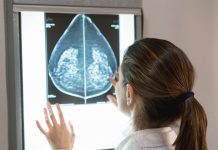

Priorities for breast cancer resources questioned after global HER2 testing survey

A global survey of HER2 testing has raised questions about how resources should be spent on potentially lifesaving HER2 targeted therapies for breast cancer,...